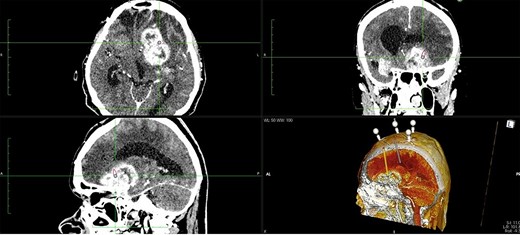

A 65-year-old female patient was presented with progressive drowsiness, cognitive slowing, poor mobility and incontinent. In addition, the patient had sensorimotor dysphagia and right-sided hemiparesis. Initial computerized tomography (CT) and magnetic resonance imaging (MRI) brain scans revealed an irregular expansive multicenter process located in the basal ganglia, frontobasal and in the area of the frontal operculum left and frontotemporal right with extensive vasogenic edema of the left frontal and parietal lobe and a compressive effect on the left lateral and III ventricle. After the administration of intravenous contrast, the process showed heterogeneous enhancement (Fig. 1). Ventricular system was dilated with a sign of transependymal edema.

The patient underwent frameless brain biopsy using the RONNA robotic system as described previously obtaining tumor tissue for pathohistological analysis [3, 7, 8]. Using RONNAplan software two trajectories were planned, one for brain biopsy on the left side and one for EVD implantation in the right side (Fig. 2). After skin perforation, twist drilling with a 4.5-mm drill, and electrocoagulation, an EVD catheter was placed in the right lateral ventricle and clear cerebrospinal fluid was obtained under elevated pressure (Fig. 3). The total operative time, including trajectory planning and surgical procedure, was 65 min.

Two separate trajectories were planned using RONNAplan software, for brain biopsy and for EVD implantation. The plan is presented in three planes with 3d reconstruction model in right lower quadrant. Orange trajectory is for brain biopsy, whereas grey one is for EVD implantation.